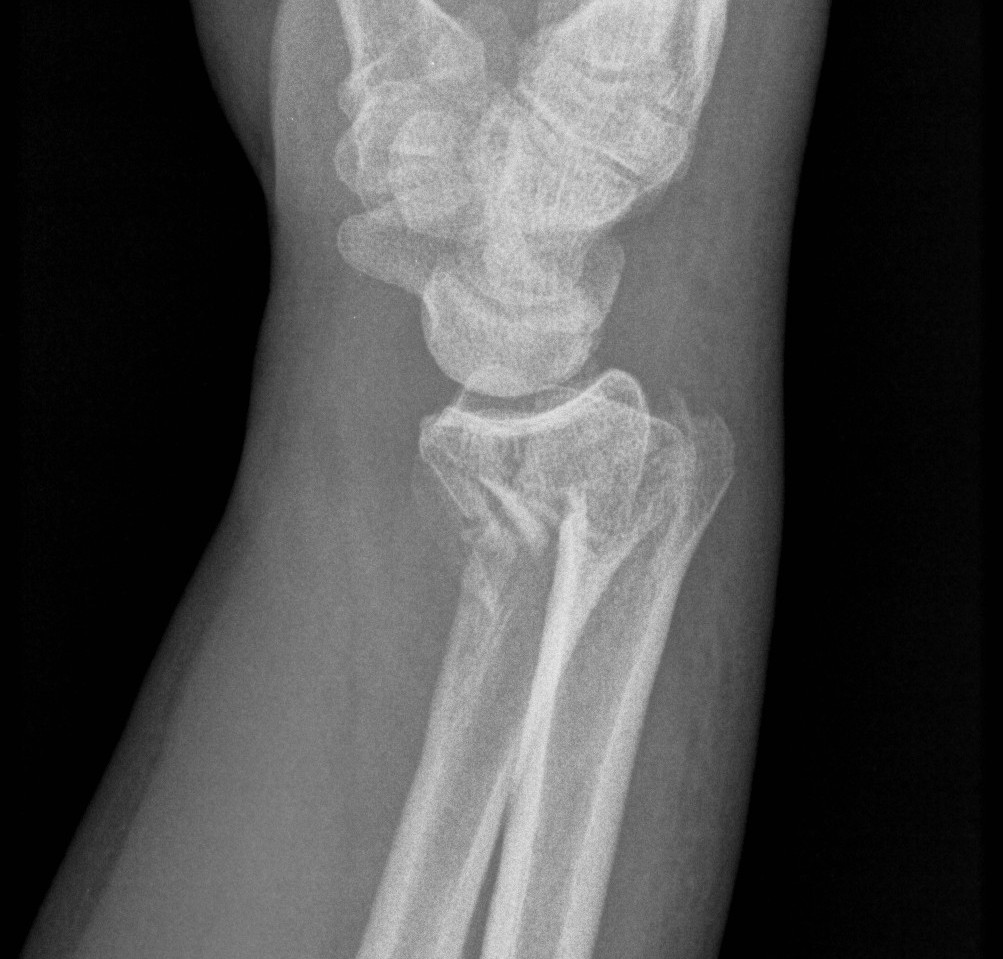

Dr shortDR short

Distal radius fracture with shortening and dorsal tilt

Distal Radius Fracture DRUJ incongruentDRUJ FractureDRUJ Fracture CT

Sigmoid notch disruption and DRUJ instability